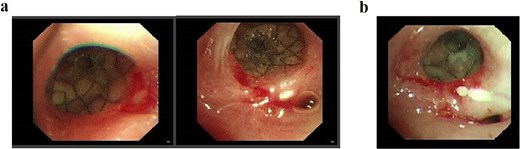

The patient received two cycles of albumin-bound paclitaxel and cisplatin chemotherapy on Day 52 and Day 76. Following the second cycle, he developed recurrent high-grade fever with productive cough. Laboratory tests revealed elevated inflammatory markers, and chest CT demonstrated severe pulmonary infection unresponsive to antibiotic therapy. Subsequent upper gastrointestinal imaging identified an esophagogastrobronchial fistula (Fig. 3a). Endoscopy revealed a 2 cm necrotic gastric wall defect distal to the anastomosis, accompanied by thickened visceral pleura and a fistulous tract connecting the right lung to the gastric lumen (Fig. 3b). Given the extensive defect and absence of intrathoracic infection, conservative measures, including fasting, gastric decompression, and nutritional support, were initiated.

(a) Upper gastrointestinal series obtained 2 months postoperatively. (b) Gastroscopic examination performed 2 months postoperatively.